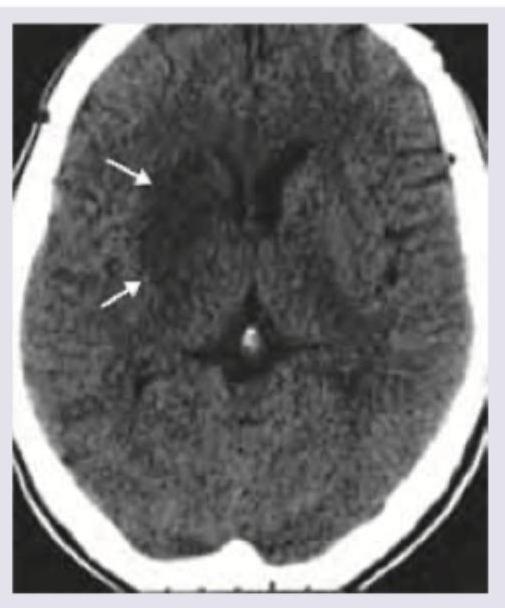

Question 16: Which of the following is correct about the NCCT shown below? (Recent NEET Pattern 2016-17)

- D. Intraparenchymal hemorrhage (Correct Answer)

Explanation: ***Intraparenchymal hemorrhage*** - The image shows a **hyperdense (bright)** lesion within the brain parenchyma, indicated by the arrows. This appearance on non-contrast CT (NCCT) is characteristic of **acute hemorrhage** (blood) within the brain tissue. - The location and morphology are consistent with blood accumulating directly within the brain substance rather than in the subarachnoid space or as a diffuse cerebral edema. *Acute ischemic stroke* - An **acute ischemic stroke** on NCCT typically appears as a **hypodense (darker)** area due to **edema** and cell death, usually after several hours. The lesion shown in the image is hyperdense. - Early signs of acute ischemic stroke (within the first few hours) can include subtle changes like loss of gray-white matter differentiation or hyperdense vessel signs, but not a distinct hyperdense parenchymal lesion as seen here. *Acute hemorrhagic stroke* - While technically a hemorrhagic stroke, this option is too broad. Hemorrhagic stroke encompasses both intraparenchymal hemorrhage and subarachnoid hemorrhage. - The specific location of the blood within the brain tissue, as opposed to solely in the subarachnoid space, makes "intraparenchymal hemorrhage" a more precise diagnosis. *Subarachnoid hemorrhage* - **Subarachnoid hemorrhage (SAH)** would appear as hyperdensity (blood) in the **sulci, fissures**, and **basal cisterns** surrounding the brain, not within the brain parenchyma itself. - The image clearly shows the lesion within the brain tissue, not in the subarachnoid spaces.